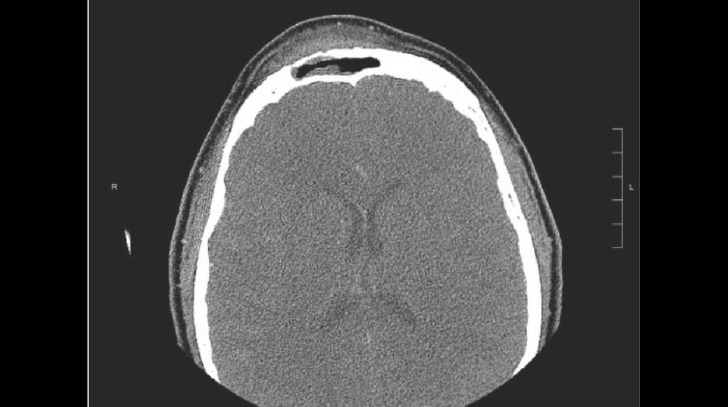

Pott肿性肿瘤(PPT)的特征是额骨骨髓炎合并骨膜下脓肿,表现为前额的局部,坚固肿胀。本报告描述了第一例记录的PPT患者在面部女性化手术后。我们报告了一个30岁的变性女性,她在接受上三面女性化手术,特别是额骨复位骨成形术和前桌额窦后退骨成形术一年后患上了PPT。患者在手术探查和彻底的冲洗以及静脉注射抗生素后病情迅速好转。重要的是,PPT解决后的美学结果令人满意,没有观察到软组织变形或不规则,损害了她之前手术的女性化效果。这个案例强调,在不牺牲性别确认程序的美学目标的情况下,可以成功地管理这些并发症。

Pott puffy tumor (PPT) is characterized by frontal bone osteomyelitis associated with a subperiosteal abscess, presenting as a localized, firm swelling of the forehead. This report describes the first documented case of PPT in a patient following facial feminization surgery. We present a case involving a 30-year-old transgender female who developed PPT 1 year after undergoing upper third facial feminization surgery, specifically frontal bone reduction osteoplasty and anterior table frontal sinus setback osteoplasty. The patient experienced rapid resolution following operative exploration with thorough irrigation, in conjunction with intravenous antibiotics. Importantly, the aesthetic outcome post-resolution of PPT was satisfactory, with no observed soft tissue distortion or irregularity that compromised the feminizing effect of her previous surgery. This case underscores that such complications can be managed successfully without sacrificing the aesthetic goals of gender-affirming procedures.